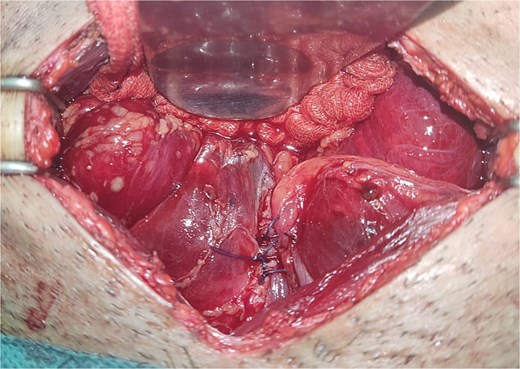

All seven cases of bladder rupture both spontaneous and traumatic were treated surgically via exploratory laparotomy to repair the injury (see Fig. 2). In both types of cases, the ruptured bladder was successfully closed (see Fig. 3). Postoperatively, Redon drain was removed on the second day, and a urinary catheter was maintained for 3 weeks to aid healing.

The image depicts the bladder after surgical repair, showing the successfully sutured rupture site and restored continuity.